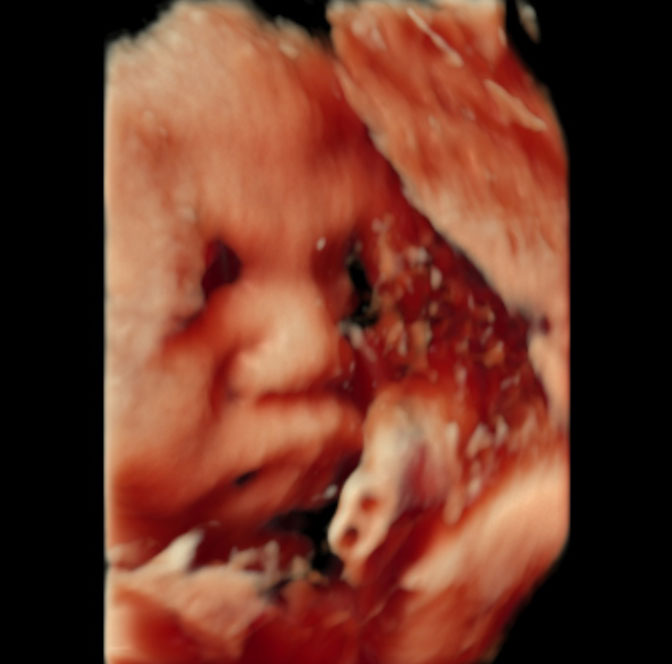

当院は4D超音波検査装置及びエコー動画閲覧サービス導入しております。

4D超音波検査では、お腹の赤ちゃんの様子をリアルタイムで見ることが出来ます。

表情や手足の動きなど、ママのお腹の中で赤ちゃんがどのように過ごしているかがわかります。

※妊婦健診時に一緒に撮影するため、4Dエコーの料金はかかりません。

4Dエコー撮影では、妊娠週数や赤ちゃんの姿勢によっては適切な画像の撮影が困難であったり時間がかかることがあります。

すべての健診時に撮影することは困難となりますのでご了承ください。

エコー動画館という、妊婦健診のエコー検査で録画した動画を、スマホやタブレット、パソコンから、いつでも閲覧できるサービスを導入しております。妊婦健診開始後より専用IDを読み取れるQRコードをお渡ししております。

ご帰宅後も、ご家族と一緒にかわいい赤ちゃんのエコー動画を御覧ください。

週数ごとの赤ちゃんの表情

妊娠13週頃の赤ちゃん